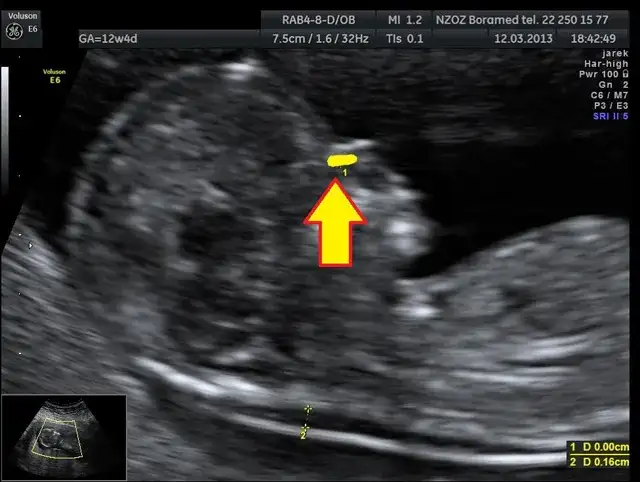

Podczas badania USG lekarze zwracają uwagę na kilka kluczowych cech anatomicznych, które mogą sugerować obecność zespołu Downa. Jednym z najważniejszych wskaźników jest przezierność karkowa, która jest mierzona w I trymestrze. Zwiększona przezierność karkowa może wskazywać na wyższe ryzyko wystąpienia tej choroby genetycznej.

Kolejnym istotnym wskaźnikiem jest obecność kości nosowej. Brak kości nosowej u płodu w II trymestrze może być również sygnałem, że istnieje ryzyko zespołu Downa. Warto zaznaczyć, że te cechy nie są jednoznacznymi dowodami na obecność zespołu, ale mogą skłonić do dalszych badań i analiz.

| Przezierność karkowa | Wzrost ryzyka zespołu Downa | Do 3 mm |

| Obecność kości nosowej | Brak może sugerować ryzyko | Obecna w 11-14 tygodniu |

Rola przezierności karkowej w ocenie ryzyka

Przezierność karkowa to miara, która jest oceniana podczas badania USG w I trymestrze ciąży. Wysoka przezierność karkowa może wskazywać na zwiększone ryzyko wystąpienia zespołu Downa. Pomiar ten wykonuje się między 11 a 14 tygodniem ciąży i polega na ocenie grubości fałdu skóry na karku płodu. Jeśli grubość ta przekracza określony poziom, może to sugerować, że płód jest narażony na ryzyko genetyczne.

Znaczenie obecności kości nosowej w diagnostyce

Obecność kości nosowej jest kolejnym istotnym wskaźnikiem, który może pomóc w ocenie ryzyka zespołu Downa. Brak kości nosowej u płodu podczas badania USG w II trymestrze może sugerować zwiększone ryzyko wystąpienia tej choroby genetycznej. Lekarze oceniają obecność kości nosowej w 11-14 tygodniu oraz w 18-22 tygodniu ciąży, co pozwala na dokładniejszą analizę.